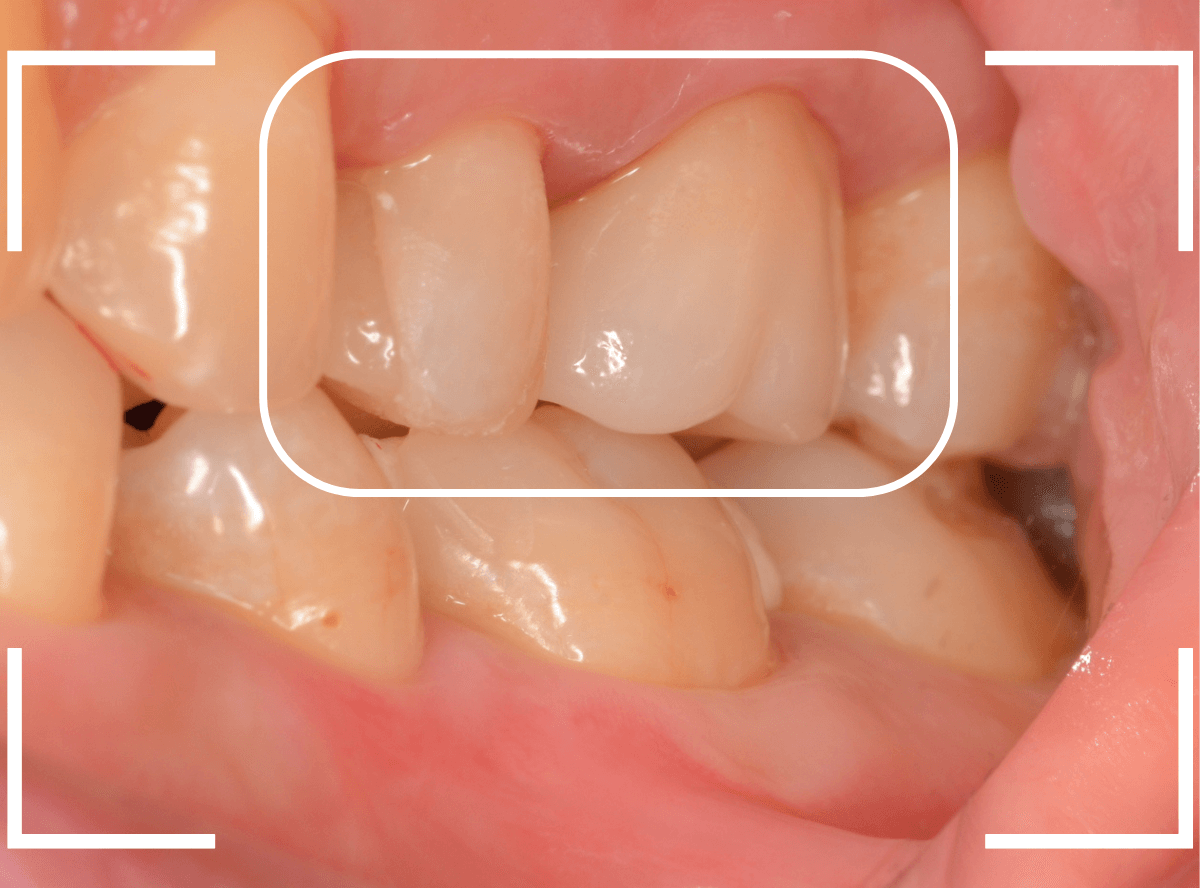

Case.16 保険のさし歯(レジン前装冠)をジルコニア・セラミックへ

以前に治療した上のさし歯を綺麗にやり直したいというご相談の患者さんです。

保険診療で行うさし歯「レジン前装冠」が入っています。

「レジン前装冠」は裏から撮影した写真を見ていただければわかるように、銀歯の上にレジン(プラスチック)を盛ったさし歯で、実質的には銀歯です。

銀歯の上にプラスチックを盛るために、歯をかなり大きく削る必要があったり、短期間で劣化・変色する(この方の差し歯も劣化してのっぺりした黄土色になっています)、金属の色素が歯肉に溶け出して歯肉が黒くなる(メタル・タトゥー)などのデメリットがあります。